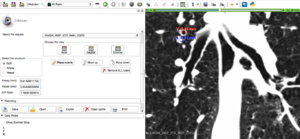

The goal of this project is to create a new semi-automated tool for SlicerCIP that allows to define bronchiectasis by means of the airway to vessel ratio. If ratio > 1, then there is bronchiectasis.

• Implement a customized Slicer editor module to select the region of interest (airway + vessel)

• Implement a tool to compute the airway to vessel ratio

• Customized Slicer module to measure airways and vessels by means of rulers created

• AV ratio is computed and shown to the user

• The SlicerCIP template is used save results and create PDF report

Illustrations

BronchiectasisModuleExample.png